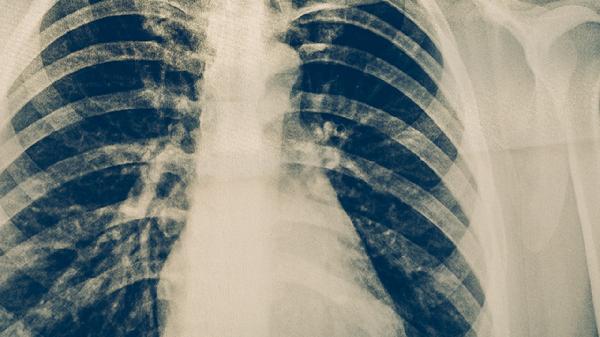

体检可以查出肺结核,但需要包含胸部X光或痰液检查等针对性项目。

常规体检项目如血常规、尿常规等无法直接诊断肺结核。肺结核筛查主要依赖胸部影像学检查和病原学检测。胸部X光片能显示肺部典型病变,如浸润影、空洞或纤维化病灶。痰涂片抗酸染色检查可发现结核分枝杆菌,痰培养能提高检出率并确定菌种。部分体检机构会提供结核菌素皮肤试验,但该检查仅提示感染风险,不能确诊活动性肺结核。

对于存在咳嗽咳痰超过两周、低热盗汗、体重下降等结核可疑症状者,建议进行专项检查。肺结核确诊需结合临床症状、影像学特征、病原学证据综合判断。单纯依靠基础体检项目容易漏诊,尤其早期病灶较小或痰菌阴性时。高危人群如密切接触者、免疫力低下者应增加检查频率。

怀疑肺结核时应到呼吸科或结核病专科医院就诊,完善胸部CT、GeneXpert等分子生物学检测。确诊患者需规范抗结核治疗6-9个月,接触者应进行预防性筛查。日常注意保持室内通风,加强营养摄入,避免随地吐痰等行为可降低传播风险。